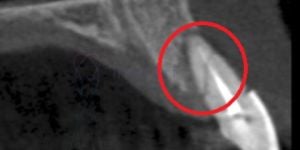

É um pino de titânio ou de cerâmica pura colocado cirurgicamente no osso maxilar ou da mandíbula com o propósito de substituir a raiz de um dente perdido. Após a instalação do implante dentário, é fixada uma coroa, uma prótese parcial ou uma prótese total, sobretudo para funcionar como dentes naturais.

- Cirurgia guiada de implantes dentário – técnica para colocação de implante de maneira pouco invasiva, confortável e indolor. Evita cortes na gengiva e algumas vezes pode ser feita com carga imediata.